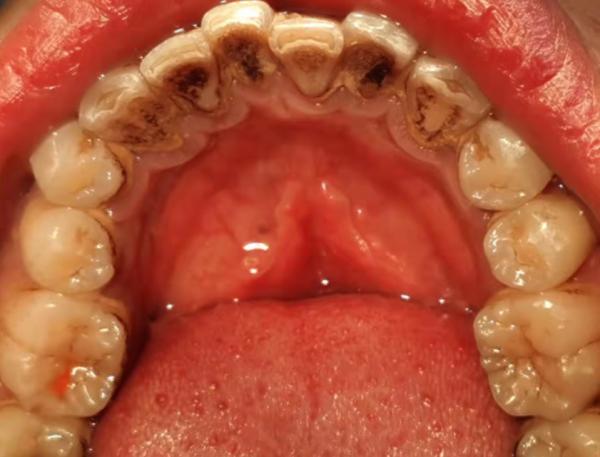

給大家看一組潔牙前後的對比圖

潔牙前